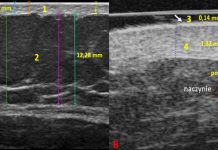

Standardy ultrasonografii w kosmetologii i medycynie estetycznej

Ultrasonografia (USG, ultrasonography) od dziesięcioleci stanowi kluczową metodę diagnostyczną w medycynie. Powszechne wykorzystywanie ultrasonografii w takich dziedzinach, jak kardiologia, ginekologia czy chirurgia naczyniowa, potwierdza...